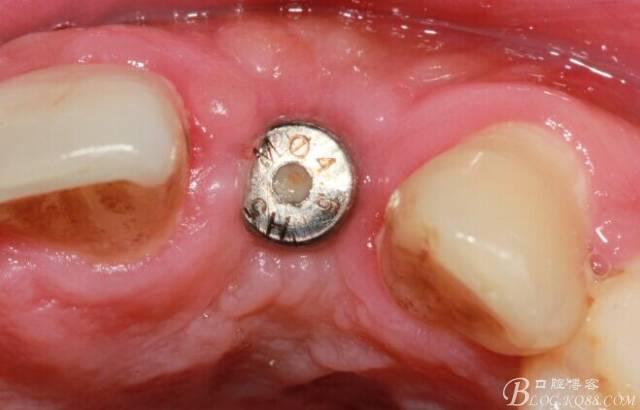

術(shù)后5個月

取模。

骨高度穩(wěn)定。